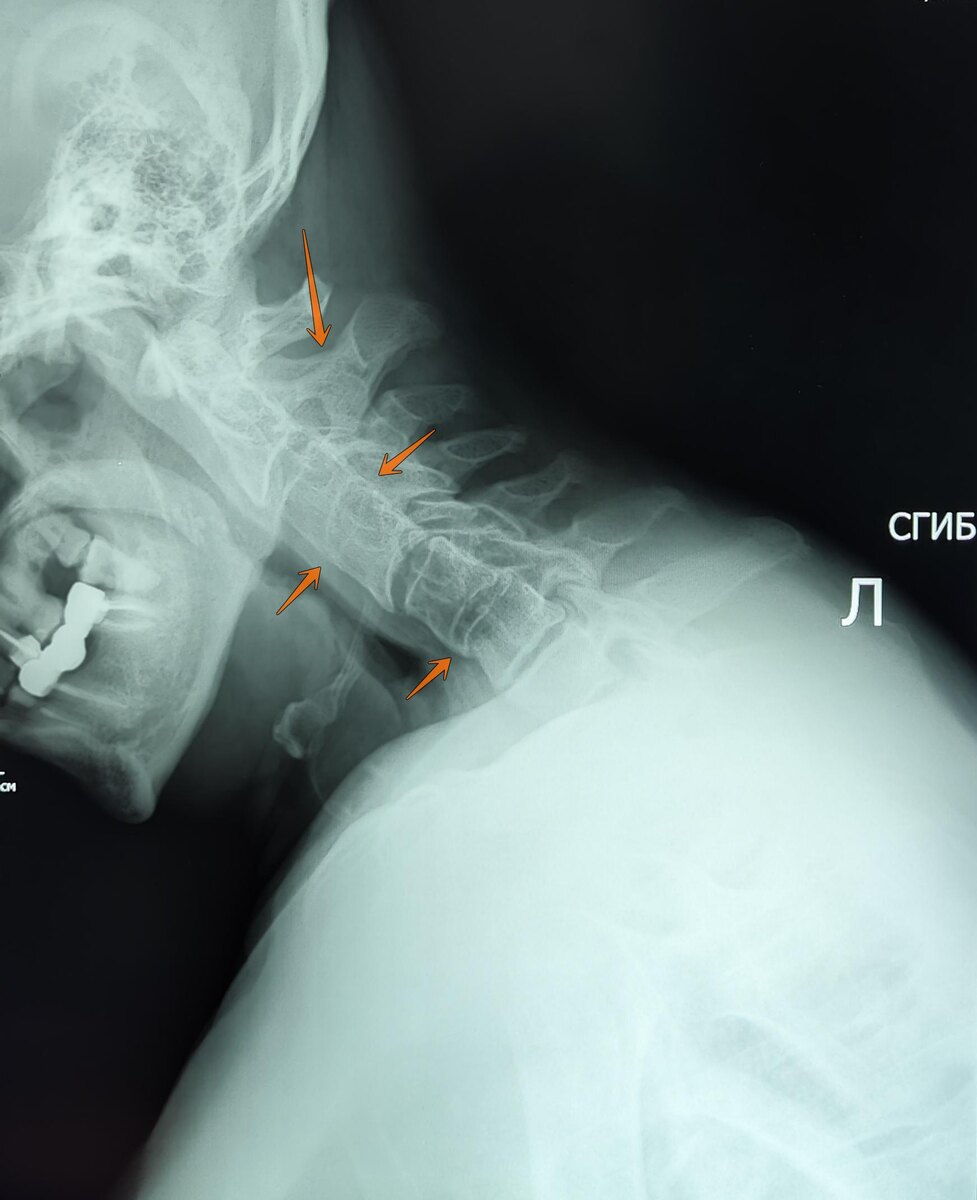

Пациент 65 лет, жалобы на боли, ограничение подвижности в ШОП.

На Р-граммах ШОП с функциональными пробами: лордоз нарушен в нижнем шейном отделе по типу кифоза. Структура тел сохранена, контуры позвонков ровные, четкие. Замыкательные пластинки склерозированы. Неравномерное умеренно снижена высота м/п пространств. Сращение остистых отростков С2-С3.Частичное сращение тел С3-С4 позвонков в переднем и заднем краях тел позвонков, за счет спондилеза. Частичное сращение передних краев тел С5-С6 позвонков за счет спондилеза. На функц.спондилограммах: отмечается умеренное ограничение подвижности в сегментах С2-С3,С3-С4,С5-С6 за счет синостоза. Заключение: Остеохондроз ШОП 2-3ст. ст. Спондилез. Спондилоартроз. Синостоз остистых отростков С2-С3.Частичный синостоз С3-С4,С5-С6.Умеренное ограничение подвижности в ШОП за счет синостоза.